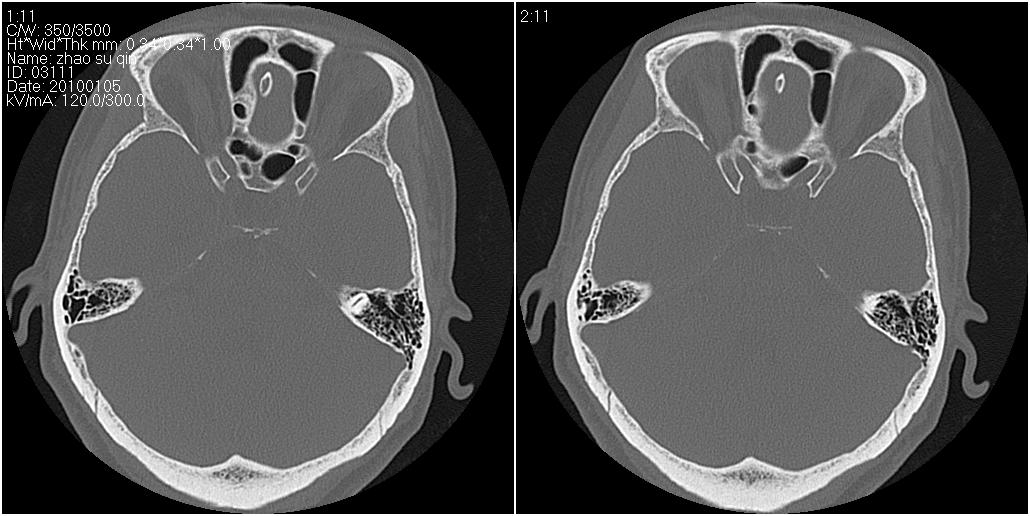

标题: CT24015:一个头部外伤患者进行鉴定,除了左侧筛板骨折,哪 [打印本页]

标题: CT24015:一个头部外伤患者进行鉴定,除了左侧筛板骨折,哪

1)左侧筛板骨折。2)双侧筛窦炎症(或积血)。

看了几遍,其余未见明显骨折征。